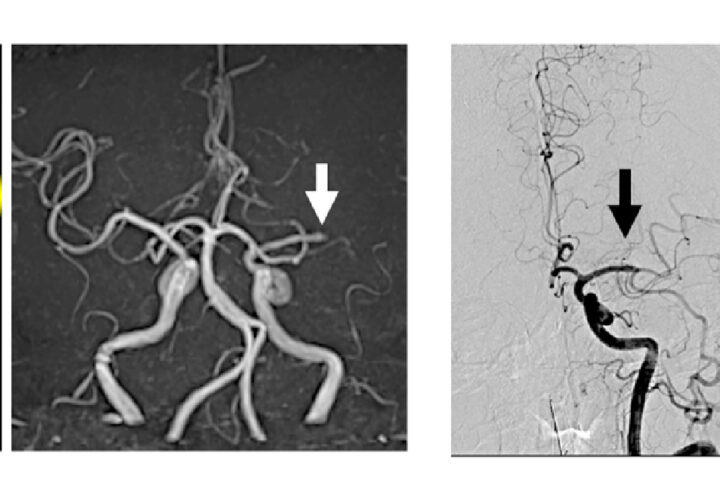

【図3】

発症から4.5時間以内であれば、全ての脳梗塞タイプに対して血栓を溶かす薬の投与(t-PA静注療法)が可能です。一方、太い血管につまった血栓を取り除く治療(血栓回収療法)は、条件を満たせば発症から24時間まで行うことができます(図2)。

血栓回収療法は、使用する血栓回収デバイスの進化や手技の向上もあり、適応が拡大しつつあります。兵庫医科大学脳神経外科が主導したRESCUE-Japan LIMIT(N Engl J Med 2022; 386 : 1303-13)という試験では、脳梗塞の範囲が広い患者さんにも血栓回収療法が有効であることを示すことができました。